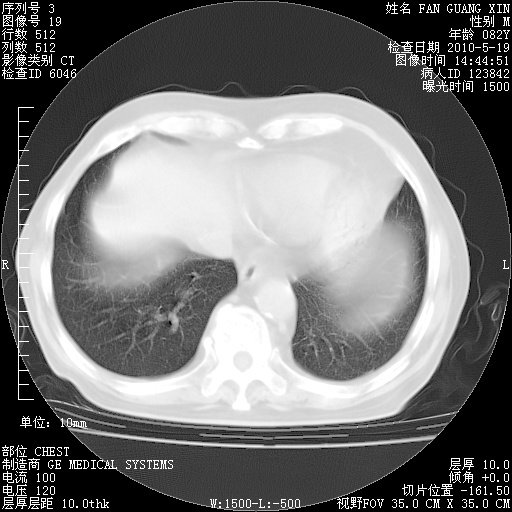

可改为口服强的松40-50mg/d治疗,若病情仍稳定,胸部阴影不再吸收可逐渐减量